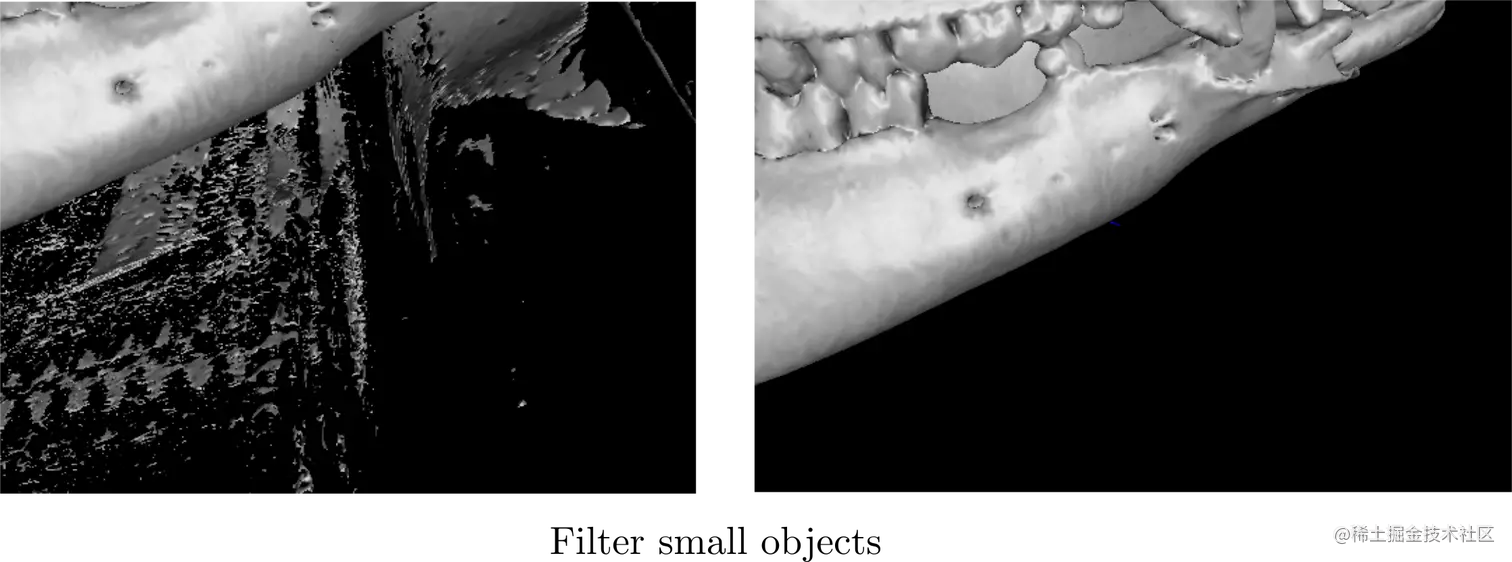

医院图像数字浏览通过PC端查看(2D 3D)